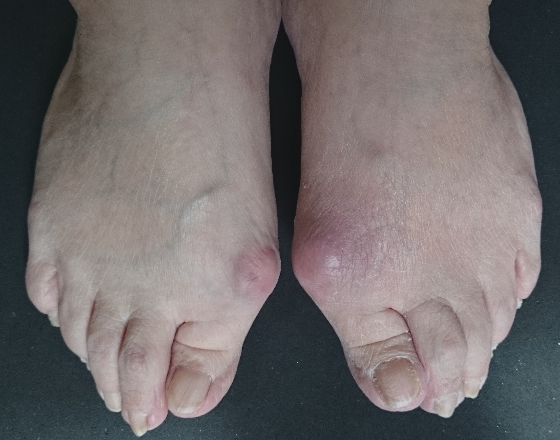

外反母趾など足の指付近の関節の変形のほとんどの症状は靴に起因し、足に合うことの無い靴が原因で発症し、悪化していきます。

数多くの外反母趾などにお困りの方に足や外反母趾などに合わせ靴を作ってきました。

そのためには・・・足のカタチと変形具合に合わせ靴を作ることで多くの方がお困りになっている足の痛みの緩和と減少、解消にいつなげることが出来ます。